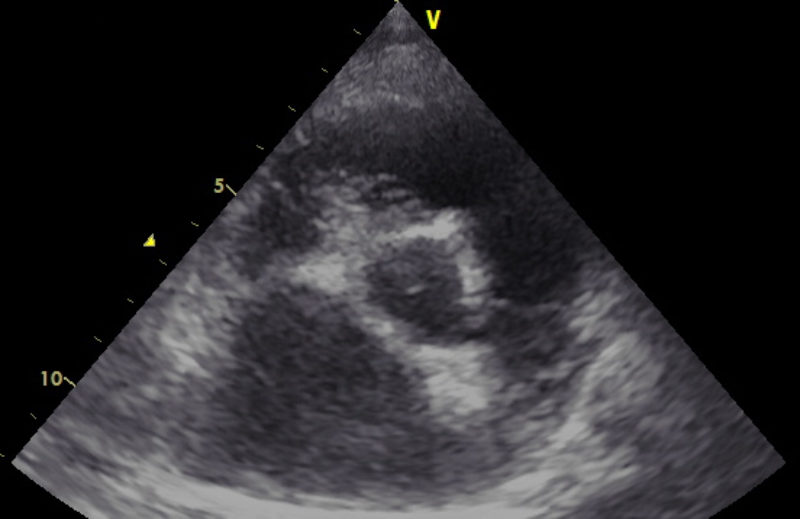

Es gibt verschiedene Ursachen für diese Form der Arrhythmie, welche mit Hilfe einer Echokardiographie weiter abgeklärt werden können. Daher wurde dem Besitzer als nächster diagnostischer Schritt ein Herzultraschall angeraten. Hierfür liegt der Hund auf einem speziellen Tisch und wird in rechter und linker Seitenlage geschallt. Im Herzultraschall zeigte sich in den Phasen, in denen „Astor“ die Rhythmusstörung hatte, eine stark verminderte Pumpleistung des linken Ventrikels mit einem subjektiv vergrößerten linken Herz (Hauptkammer und Vorkammer). Was sich dann auch in den Messwerten bestätigte. In Phasen, in denen der Herzschlag einen normalen Rhythmus hatte, war die Pumpleistung etwas besser, die Messwerte lagen im Graubereich. Der linke Vorhof war leicht vergrößert. Neoplasien oder Veränderungen im Herzmuskel konnten nicht dargestellt werden.